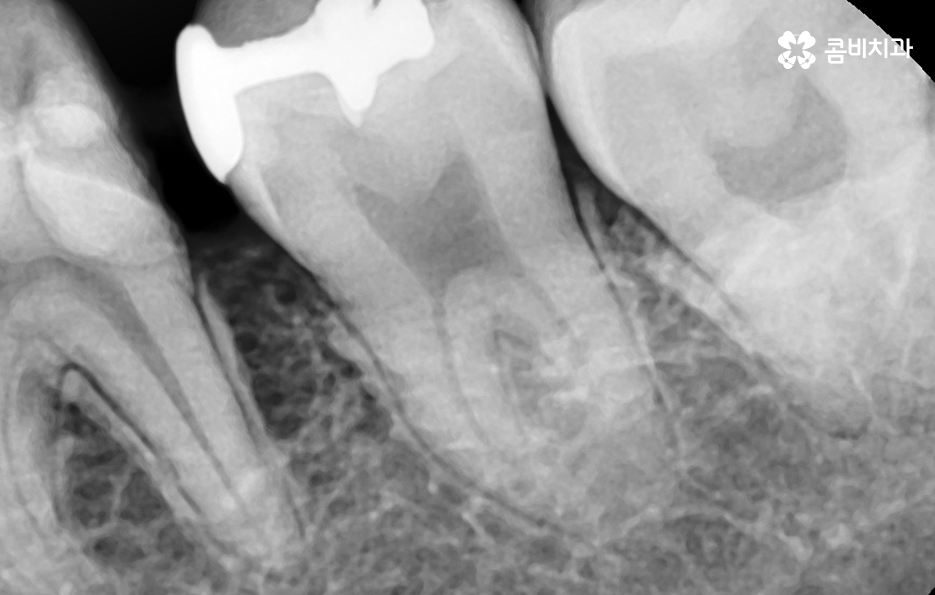

치아 수명이 다하여 결국 발치로 이어지는 시점은 주로 치아의 뿌리 손상을 기준으로 판단하게 되기 때문에 치아 뿌리 손상까지 이어지지 않도록 충치를 미리 예방하고 치료하는 것이 가장 기본적으로 중요하겠고 치아의 신경조직은 치아에 영양분과 수분을 공급하기 때문에 치아 손상이 발생되었을 때 신경치료로 이어지기 전에 치료하는 것이 중요할 거예요

치아 인접면에 발생된 충치가 신경치료나 뿌리 손상으로 이어지지 않도록 미리 막는 것이 중요하며 충치 치료를 할 때 자연치아를 되도록 보존하는 치료를 하는 것도 하나의 방법이 될 수 있어요

위에 보시는 것처럼 금 인레이의 경우 치아의 삭제를 줄일 수 있는 치료 방법으로 금 인레이 자체가 내구성이 튼튼하고 생체친화적이며 얇게 제작을 해도 어금니 처럼 강한 압력을 받는 치아에도 치료가 가능하기 때문에 치아 보존에 유리한 재료라고 할 수 있는데요